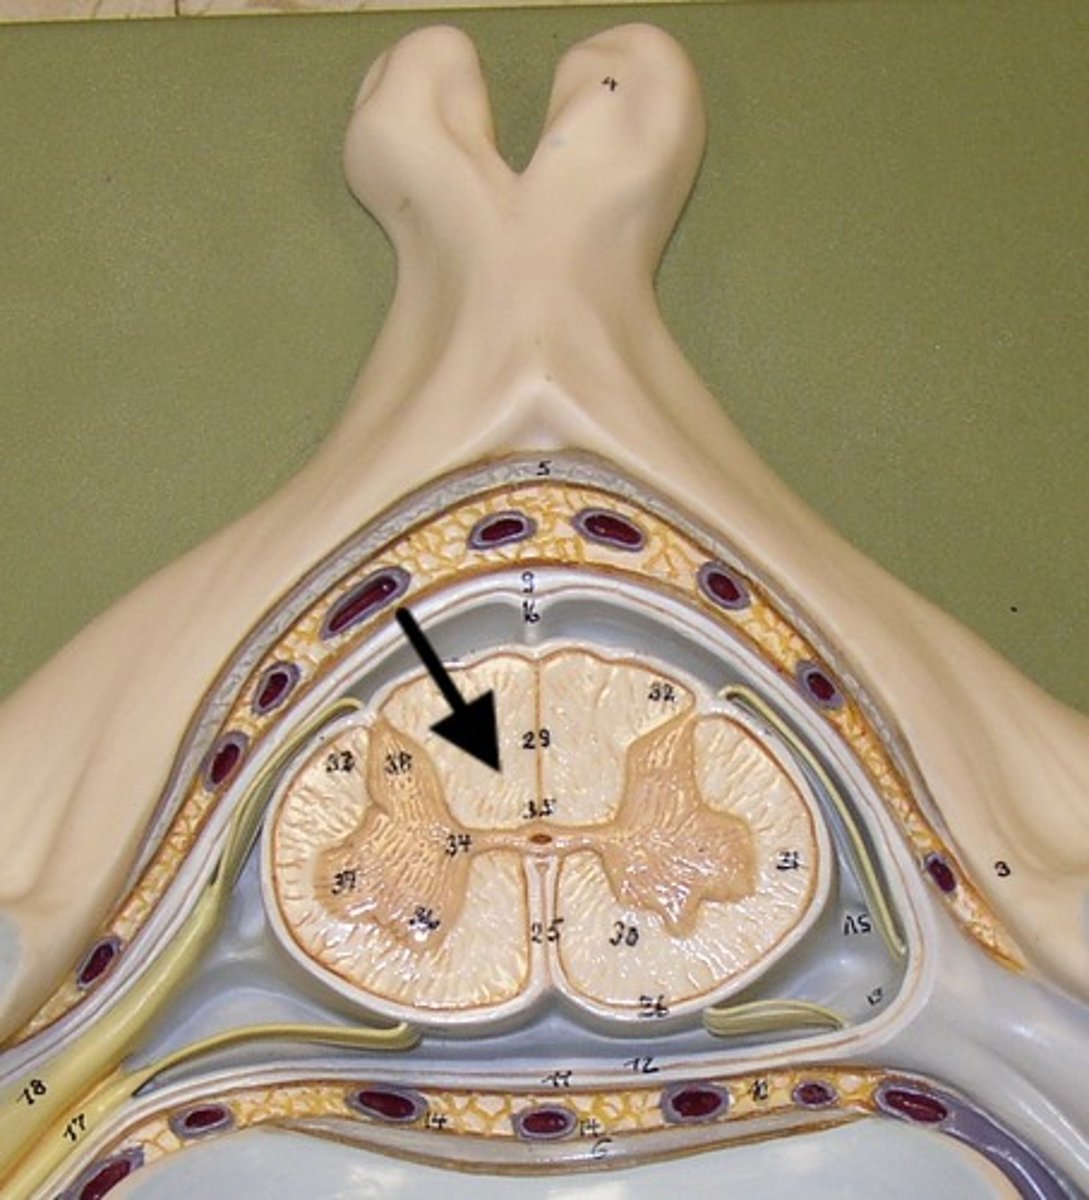

posterior gray horn

A

Location of sensory nuclei

lateral gray horn

B

Contains Motor nuclei (visceral)

only in thoracic and lumbar vertebrae

anterior gray horn

C

Contains Motor nuclei (Somatic)

posterior white column

Sends information up to the brain

lateral white column

Information descends from the brain

anterior white column

Information descends from the brain (Brings info back to the spinal cord)

central canal of spinal cord

contains cerebrospinal fluid